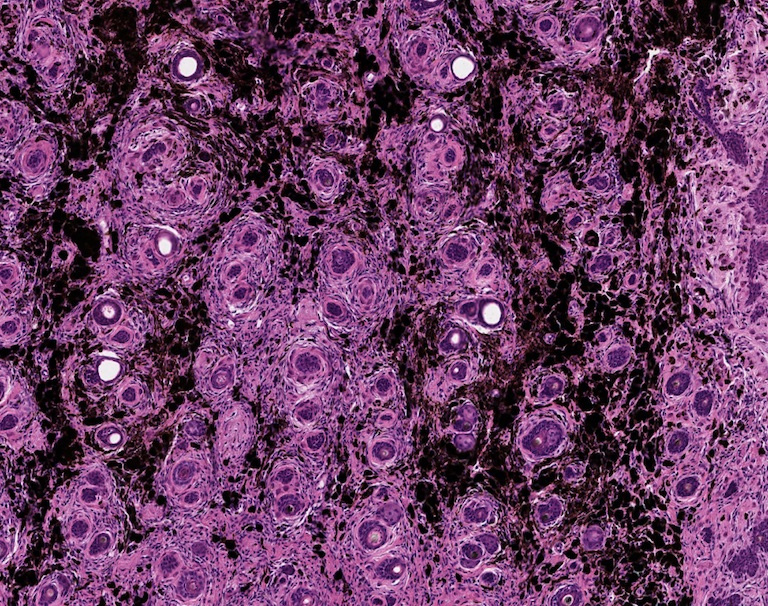

Lymphocytes Infiltrate Melanoma Cells 2

These H&E images depict melanomas undergoing immunotherapy treatment. The images show high infiltration of lymphocytes, the immune system’s effector cells against tumors, in a mouse melanoma model that is considered very challenging. In this images, swarms of lymphocytes can be identified by their small, dense nuclei, and pockets of brown melanin produced by the tumor can be seen throughout.